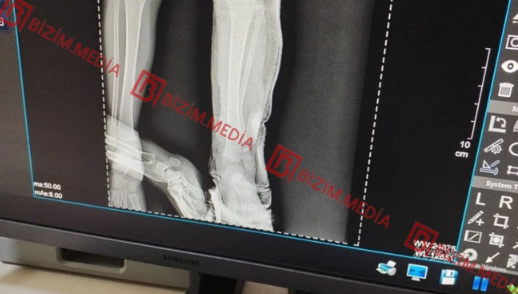

Şikayətçinin sözlərinə görə ilk dəfə 2022-ci ilin iyulunda qızının qolunda yanıq izləri görüb. Məlum olub ki, isti qaşığı 5 yerdən uşağın qoluna basıb və I dərəcəli termiki yanıq yetirib:

"Bundan başqa, müxtəlif vaxtlarda – 2023 və 2024-cü illərdə dəfələrlə taxta əşya ilə döyərək sifətinə və yanaq nahiyəsinə xəsarətlər yetirib. İndiyədək azyaşlı qızıma əziyyət verir. Digər kiçik qızıma da ehtimal ki, eyni davranışı sərgiləyir. Hər iki övladımın psixoloji durumu korlanıb. Bu azmış kimi uşaqları nəzarətsiz buraxır. Bu yaxınlarda kiçik qızımı avtomobil vurub, amma qadın bizi aldadaraq evdə yıxıldığını deyib. Kiçik qızımın ayağının biri qırılıb, yeriyə bilmir, gipsdədir və uzun müddət müalicəyə ehtiyacı var".